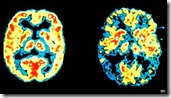

Imagens apresentadas no artigo do The Economist que sugere a possibilidade de fungos provocarem o Alzheimer

O dr. Carrasco e sua equipe examinaram o tecido de 25 cadáveres, 14 dos quais pertenciam a pessoas que tiveram a doença de Alzheimer quando vivos. Os outros 11 tinham uma idade média de 65 anos, sendo livres de Alzheimer, contra 82 dos que haviam sofrido a doença. A amostra é reconhecidamente pequena, mas dá indicações de que havia sinais de células fúngicas de vários tipos em seus neurônios, sendo que os outros não tinham sido infectados.